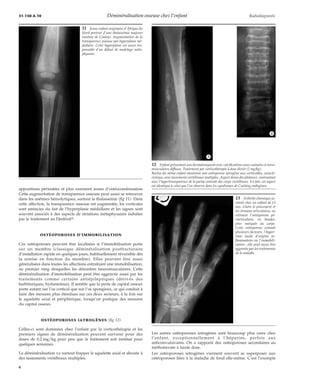

1 Cliché de main d’une

patiente porteuse d’un syn-drome

de Turner. Là, l’os-téoporose

est évidente, avec

des corticales minces et une

augmentation de la trans-parence

osseuse des méta-carpiens.

Ceci traduit une

perte du capital osseux d’au

moins 30 %.